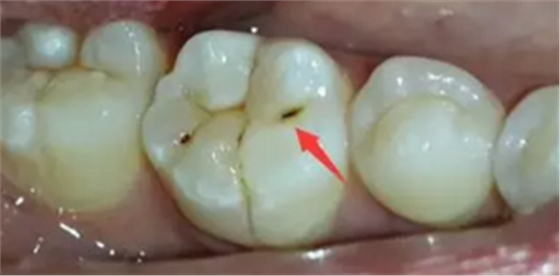

蛀牙從外表看就表現(xiàn)為一個黑點,通常位于窩溝點隙(牙面上點狀或線狀凹陷)

淺齲——侵犯牙釉質(zhì):起初的蛀牙只限于牙齒表面淺層,牙面上會出現(xiàn)一個小黑點,不痛不癢,所以很容易被我們忽視。